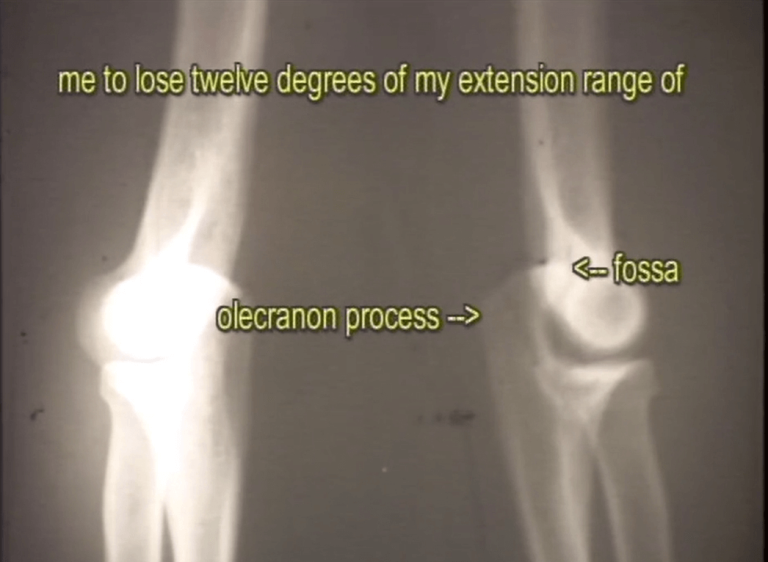

X-Ray Analysis: Diagnosing Pitching Arm Damage Through Science

Dr. Mike Marshall’s biomechanics pitching reform began with X-ray analysis in 1967—documenting damage caused by traditional pitching mechanics.

He measured biomechanical discrepancies between the pitching and non-pitching elbows, including loss of range in extension and flexion. The results revealed early-stage injury patterns that feel-based coaching failed to detect.

Below are 1967 x-rays of Marshall’s elbows, which show twelve degrees loss due to throwing the traditional pitching motion.

1967 X-ray of Dr. Mike Marshall’s elbows showing loss of extension in pitching arm—foundational to his biomechanics pitching reform philosophy.

1967 X-ray of Dr. Mike Marshall’s elbows showing loss of flexion in pitching arm—documenting early-stage injury mechanics missed by feel-based coaching.